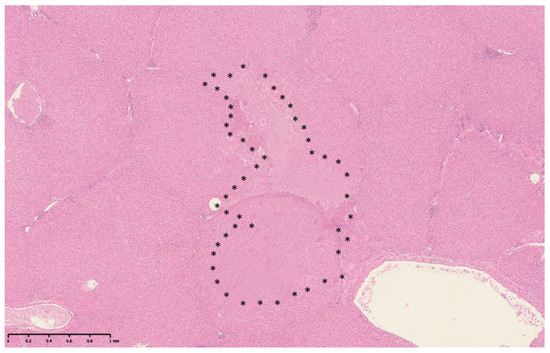

Three-Dimensional Reconstruction